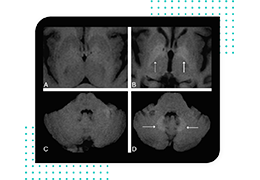

Eclipse 成像智能功能提供强大的处理能力和最佳质量的影像,同时减少质量错误并提高剂量效率。

凭借 AI、专有算法和先进的影像处理能力,提供出色的影像质量和无与伦比的诊断信心。

与标准影像处理相比,智能降噪功能可使客户降低辐射剂量,而不会损失影像质量。这在新生儿和儿科成像中尤其重要,在这种情况下以尽可能低的剂量成像至关重要。

提供相配视图选项,以减少所需的曝光次数,并提供更清晰的感兴趣区域视图。